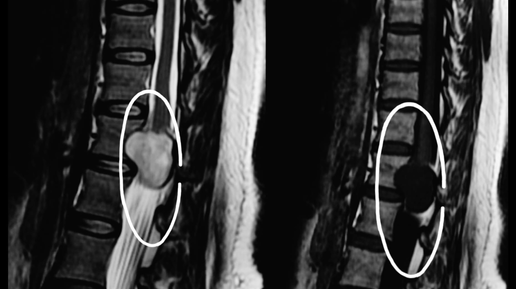

Невринома через 12 лет после лечения - разбор реального случая

Центр «Гамма-нож» Москва является первым в России центром, который продолжает наблюдать за отдаленными 10 лет и более результатами радиохирургического лечения своих пациентов, что представляет большой интерес для отечественной медицины. Женщина, 49 лет При обследовании по поводу снижения слуха на левое ухо по данным МРТ головного мозга выявлена невринома в проекции левого мостомозжечкового угла с перифокальным отеком, распространяющимся на область левой гемисферы мозжечка...